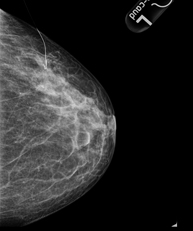

Mammography

Mammography tests use low-dose x-ray imaging to detect breast tissue pathologies (especially breast cancer) in gynaecological screening and targeted diagnostics. Mammography can be interventional with cyst puncture, stereotactic biopsy, pre-surgical marking, and galactography.

Digital mammography

Digital mammography is an innovative breast examination technique that uses a low radiation dose, thus reducing exposure compared to conventional mammography. The image is digitised using special cassettes on a system known as CR (Computed Radiography). These digitalisation techniques provide excellent images, especially in breasts that are difficult to examine, such as glandular breasts, which appear dense on mammograms, enabling better detection of tumours in this group of patients.